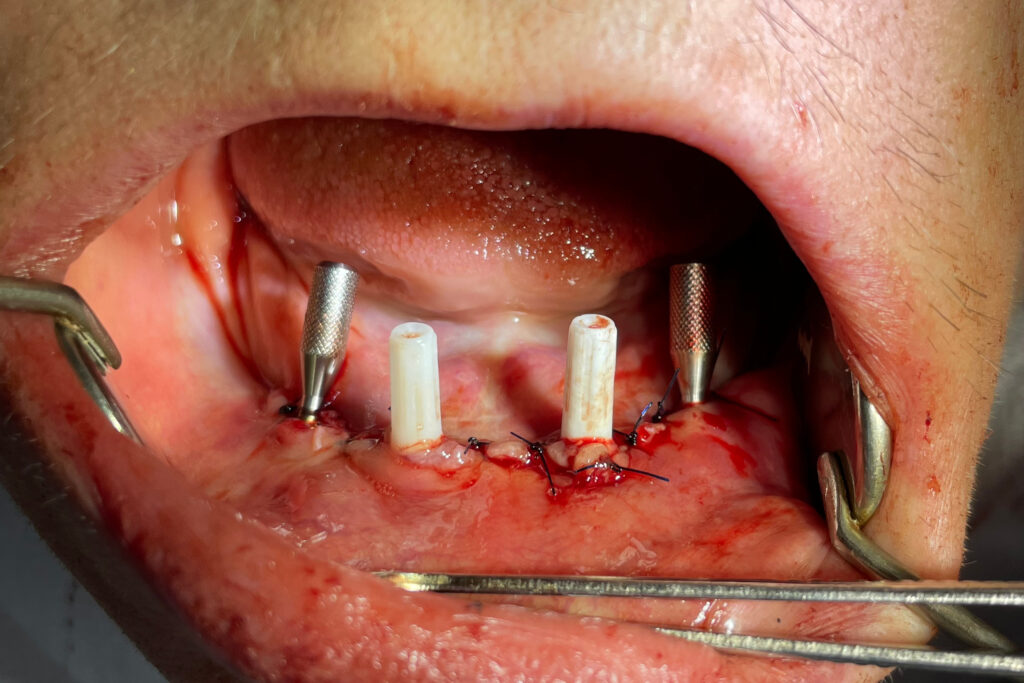

После проведенной консультации было принято решение об удалении зубов на нижней челюсти, которые находились в неудовлетворительном состоянии и проведении комплексной имплантации по системе All-on-4.

После установки 4х имплантантов Megagen Anyone были сняты оттиски для изготовления металлоакрилового протеза на нижней челюсти и для съемного протеза на верхней.

имплантация

Это фото может содержать тяжелый для восприятия контент